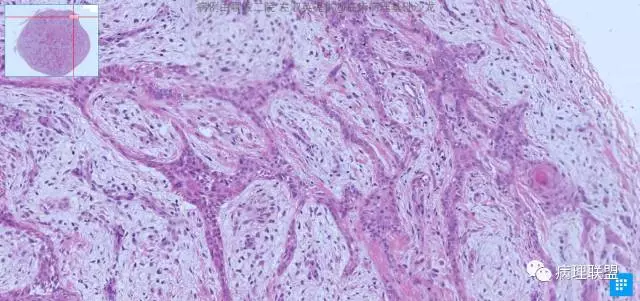

总结毛囊瘤,毛囊瘤有个中心,好多时候看不到这个中心,但是它有放射状分布的毛源分化,并且这个毛源分化在纤维的间质中,,后面还有个毛鞘棘皮瘤,它也是放射状分布,但是它分布的间质是类似胶原红的。还有不同之处,等读到了那个病我们再鉴别,一看图就会明白的。这个地方有可能就是那个中心,有可能没切出来,还是放射状分布的,有毛源分化的,就是没有5.1典型

我们一定要在典型中找不典型,不典型中找典型,5.2不典型病例,可以找到典型的毛囊分化,大多是不典型地方。真皮限局性肿瘤,都是低倍一看很清晰的。正如魏老师说的,如人形舞蹈,如飞禽走兽。